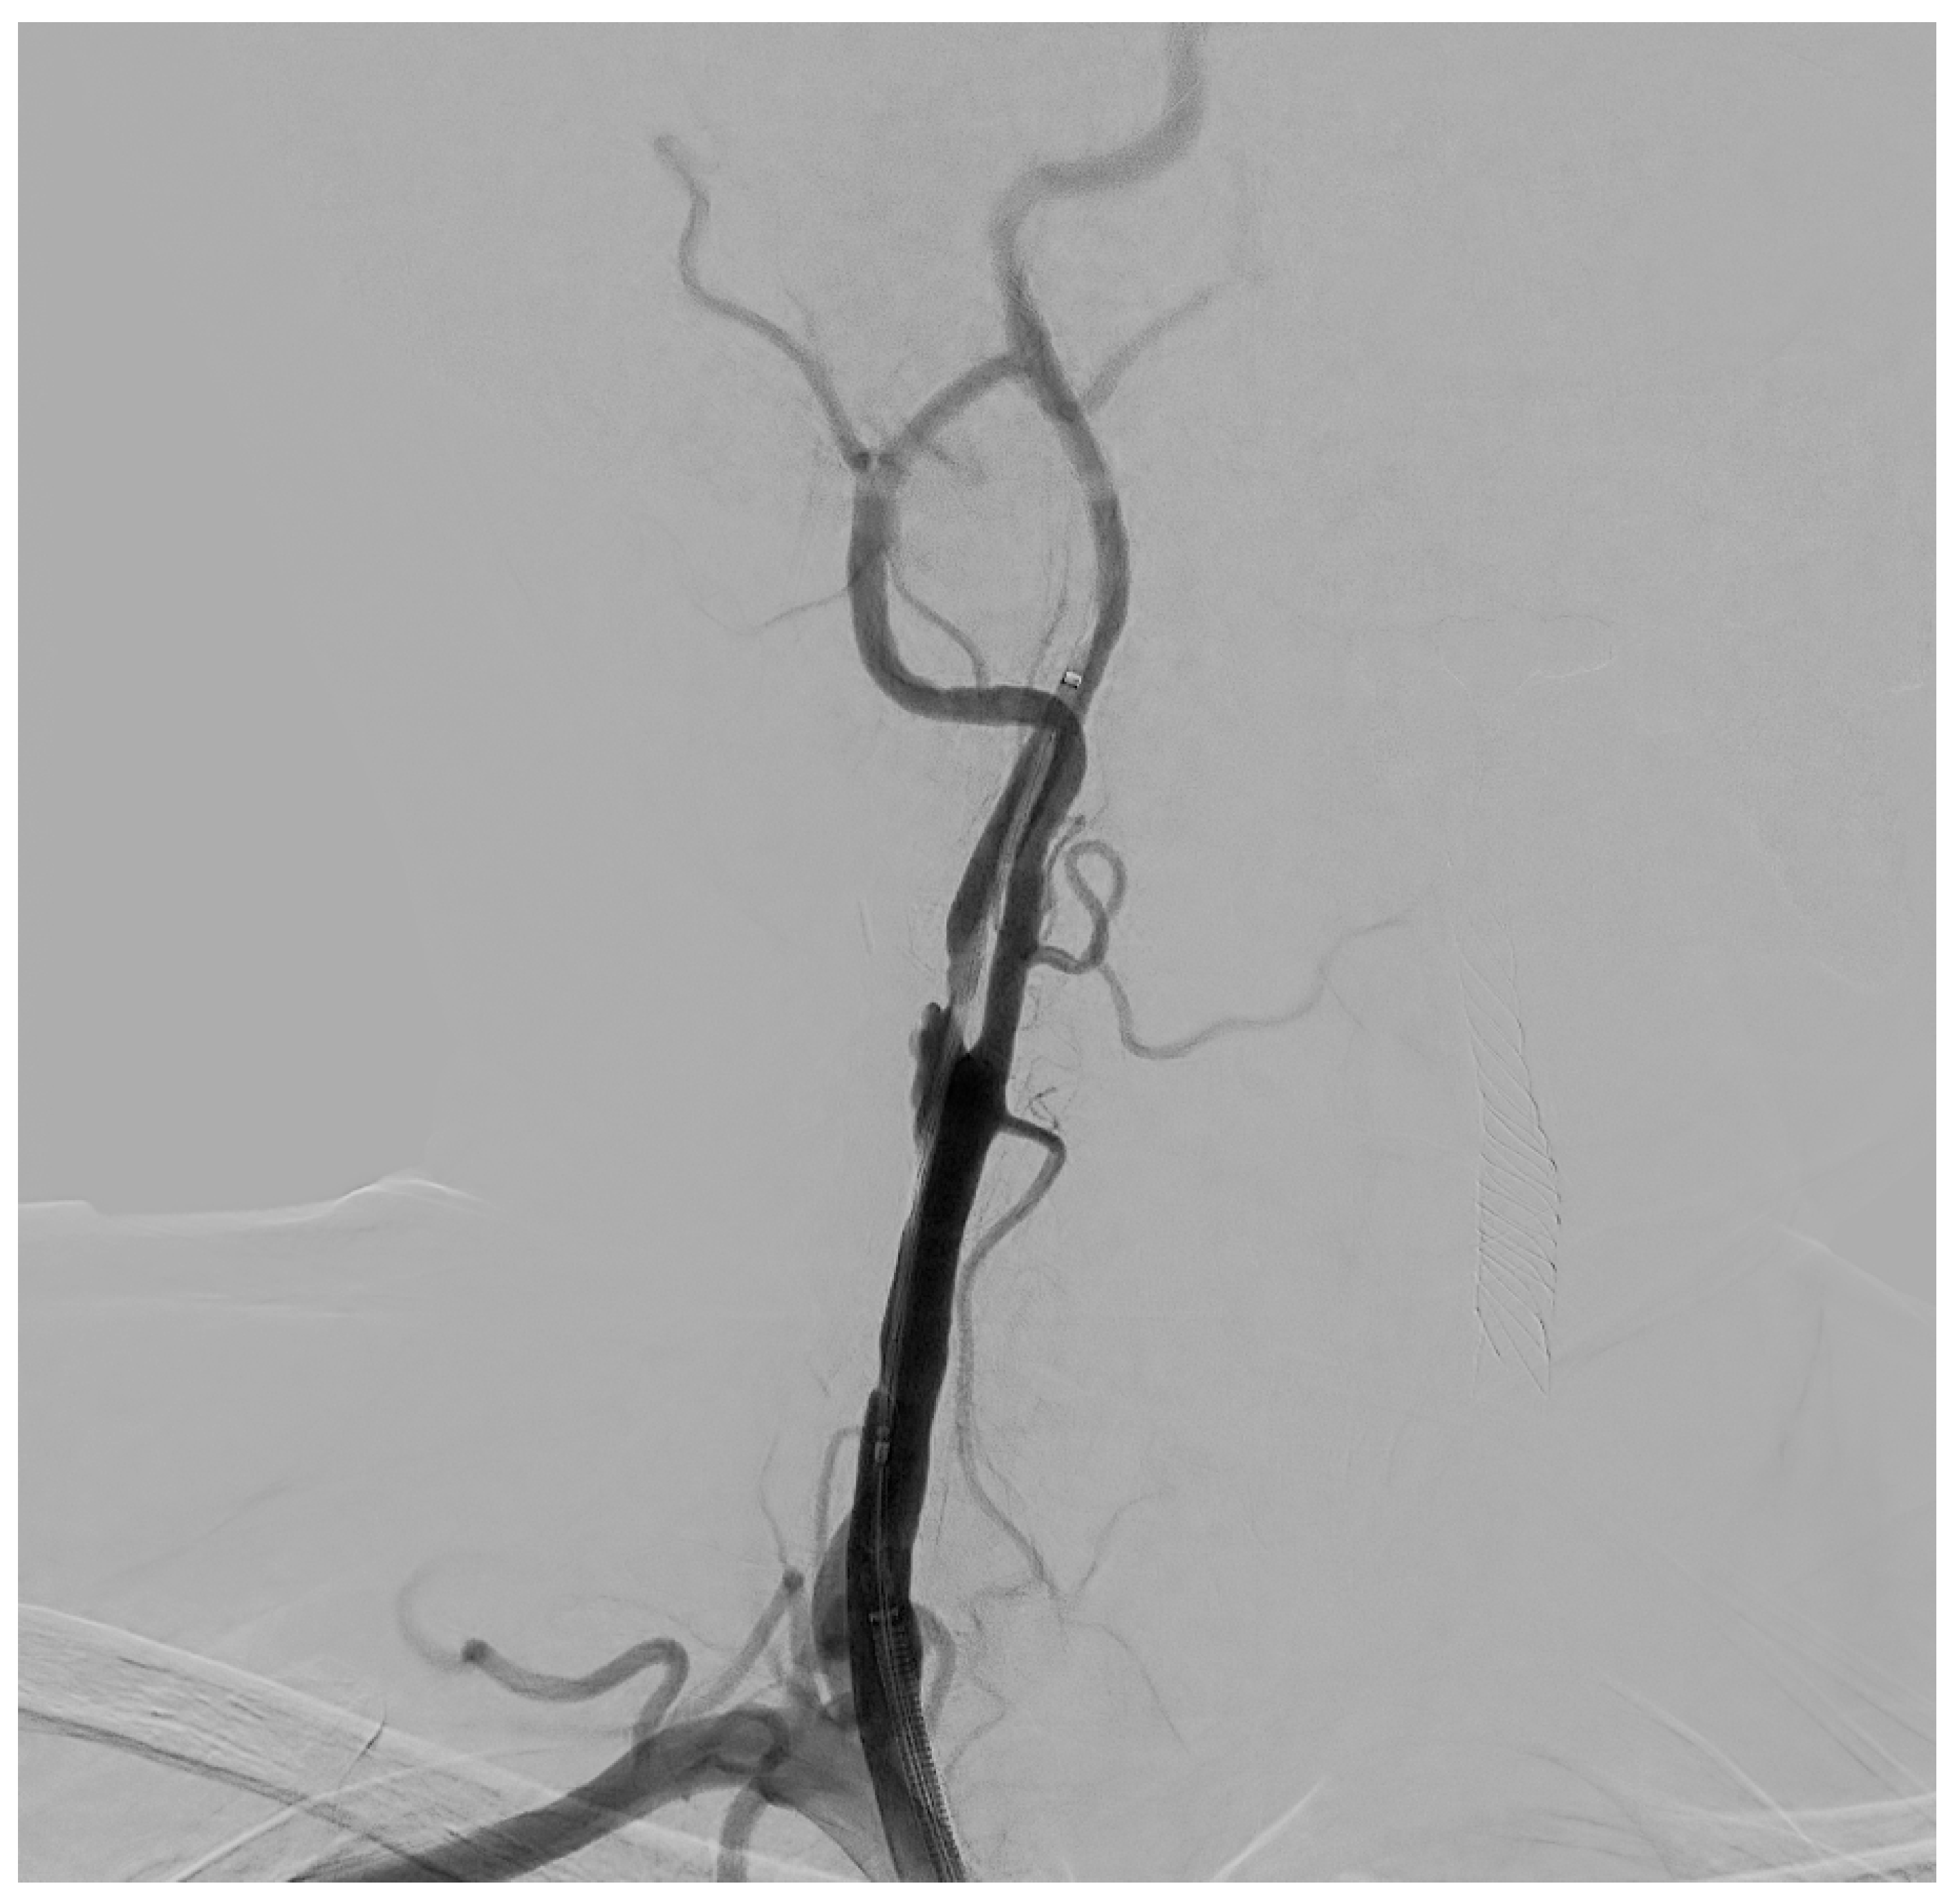

The procedure is performed in the angiographic suite, under mild sedation to monitor the neurological status of the patient, by arterial vascular access, usually femoral. With the wire–catheter system, the common carotid artery (CCA) of the pathological side is selectively catheterized and a diagnostic angiography is performed to identify the stenosed area (Figure 3). The stenosis carotid tract is crossed through the wire–catheter system, and only after the placement of a neuroprotection device in the ICA, a balloon angioplasty is performed to compress the atheromatic lesion and restore the original luminal vessel diameter. Regarding neuroprotection, today we have two classes of embolic protection devices available: a coaxial umbrella-like filter positioned in the distal ICA (Figure 4) or hemodynamic balloon block systems with reversal flow that can be placed either proximally or distally to the carotid stenosis with overlapping results in reducing the distal embolic phenomena risk but with a higher rate of periprocedural vasospasm in the case of a distal umbrella-like filter [53]. At this point, it is necessary to inject 1 mg of atropine to avoid vasospasm before releasing a permanent endovascular stent. We have three types of endovascular stents such as open-cell, closed-cell, or double-layer (Figure 5). Open-cell stents were worse than closed-cell due to the higher degree of plaque protrusion and the procoagulant state induced by the stent that can trigger embolic phenomena, recording a higher rate of stroke or restenosis at 30 days. The double-layer stents are still in the process of approval by the FDA although they have shown in some clinical trials strongly encouraging results with a risk of adverse events at 30 days <2% [54].

Figure 3. Selective DSA (Digital Subtraction Angiography) of right CCA showing significative (>50%) stenosis of right ICA, in post-ostial tract.